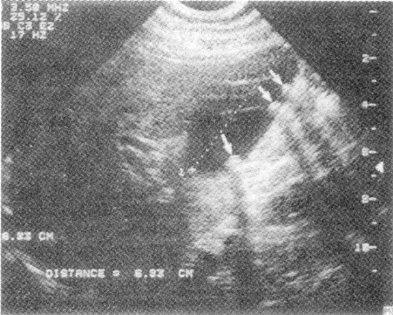

Весьма информативно УЗИ. С его помощью удается определить размеры и форму желчного пузыря, толщину его стенки, наличие в нем конкрементов, их количество и величину (рис. 8). Особое преимущество метод имеет перед рентгенологическим в выявлении конкрементов холестериновой природы. По точности он превосходит рентгеновскую холецистохолангиографию, по нашим данным, не менее чем в 2 раза.

Рис. 8. УЗИ желчного пузыря. Определяются три камня (указаны стрелками) с акустическими тенями.